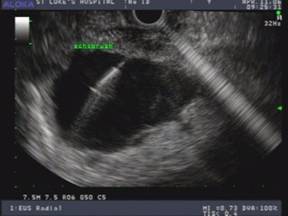

The EUS appearance of mucinous cystic neoplasm is variable. They are commonly associated with a visible wall and septations of variable thickness, and peripheral calcifications can be seen in some cases (Figures 1 and 2) [43]. Invasive malignancy has been associated with the presence of thick or irregular cyst wall, intramural nodules or solid components and larger cyst size (Figure 3) [14]. EUS-FNA cytology could reveal columnar epithelial cells in up to half of the patients in association with extracellular mucin [34, 46]. Mucin is frequently identified on EUS-FNA of mucinous cystic neoplasm and cyst fluid is typically clear with elevated CEA levels and low amylase. Mucinous cystic neoplasms are premalignant lesions but the risk of malignant degeneration is likely less than that of IPMN [45]. The risk of malignancy in these tumors described in a series of 163 patients was found to be 17.5% [47]. Therefore, surgical resection is recommended for all surgically fit patients. The prognosis after surgery for mucinous cystic neoplasm that have not undergone malignant transformation is excellent and the 5-year survival for mucinous cystadenocarcinomas post resection exceeds 60% [6, 48].

Figure 2. a. CT scan of the abdomen in a 56-year-old female with left upper quadrant pain demonstrates a unilocular pancreatic tail cyst. The cyst wall has variable thickness but does not demonstrate any nodularity. No solid mass was noted. Pseudocyst was suggested in the differential diagnosis of this lesion. b. EUS appearance of the same cyst in A. Thick mucoid cyst content appears granulated on ultrasound, but no visible septations or solid lesions demonstrated. c. Gross surgical resection specimen for the same patient (distal pancreatectomy with splenectomy). No malignancy was detected in this specimen. d. Photomicrograph of a mucinous cystadenoma (H&E, 400x). Columnar mucinous epithelial cells are seen overly ovarian stroma, which is a hallmark of these tumors. |